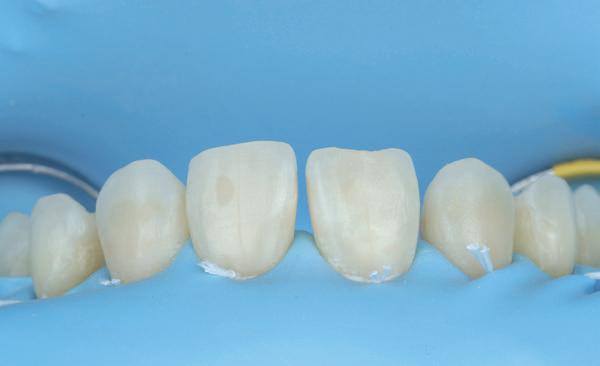

Een 47-jarige vrouw wordt aan het einde van het orthodontische traject door haar eigen tandarts naar mij verwezen voor een intake en eventuele behandeling. Bij mevrouw zijn elementen 12 en 22 afwezig. De 13 en 23 zijn gemesialiseerd. Haar eigen tandarts vraagt of ik het front met composiet kan restaureren om weer een harmonieuze glimlach te krijgen (Afbeelding 1).

Tijdens de intake wordt een complete lichtfoto status gemaakt om de positie van de elementen goed in kaart te brengen en een behandelplan op te kunnen stellen. Op de close-up foto van het bovenfront (afbeelding 2) zien we dat er sprake is van slijtage aan element 11. Elementen 12 en 22 zijn afwezig en elementen 13 en 23 zijn gemesialiseerd. Tussen element 11 en 13 is er sprake van een diasteem. Dit diasteem is niet aanwezig aan de andere zijde (afbeelding 3).

Nadat de vaste apparatuur verwijderd is (afbeelding 7 en 8), zie ik mevrouw voor het maken van een afdruk/scan ten behoeve van een wax-up. Aangezien ik in deze casus wil werken met de injectietechniek, is een wax-up noodzakelijk.

Voor een wax-up ten behoeve van opbouw met composiet worden strengere eisen gesteld dan aan een motivational wax-up. Wanneer je de wax-up wil gebruiken voor het overzetten met composiet, is het belangrijk om een nauwkeurige transparante mal te hebben (Exaclear, GC). Deze mal moet transparant zijn om voldoende licht van de polymerisatielamp door te laten om zeker te weten dat al de composiet goed uithardt. Verder is het belangrijk om te weten dat Exaclear een ontzettend nauwkeurig materiaal is. Dit houdt in dat je een exacte kopie zult maken van de wax-up. Alle foutjes en oneffenheden in de wax-

up zullen dus ook overgezet worden in de mond. Om de situatie van de wax-up zo goed mogelijk om te zetten in de mond is het daarnaast belangrijk dat je mal voldoende afsteuning heeft. Dit kun je doen door sommige elementen of delen daarvan niet te laten opwassen (in dit geval de palatale zijde van de elementen).

12: Rubberdam isolatie met behulp van flossligaturen om zoveel mogelijk retractie van de gingiva en weke delen te krijgen.

13: Occlusaal aanzicht na het isoleren met teflon.

14: De transparante mal wordt gepast en eventuele interferenties worden verwijderd.

15: Na het injecteren met G’aenial Universal Injectable A2 wordt

Over de wax-up heeft de tandtechnieker een puttymal gemaakt en de wax-up wordt overgezet in de mond met behulp van een bisacryl (Luxatemp Star A2, DMG) (afbeelding 9-11). Nadat de wax-up / mockup is goedgekeurd, wordt een afspraak gemaakt voor de daadwerkelijke omzetting in composiet.

de overmaat verwijderd met een scalpel.